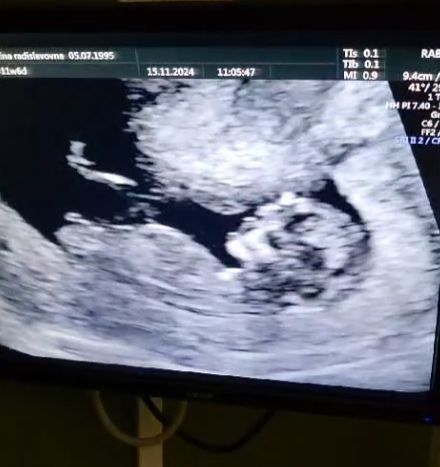

Я легла и меня попросили снять всю нижнюю часть одежды до колен. Девушка не стеснялась класть свою руку мне прям на лобок опираясь на него. Я не стеснялась, просто это было странно. Но, так как это моя первая беременность и первое УЗИ, решила, что ну наверное так надо. Пока она смотрела ребенка, она ни слова не говорила. Только диктовала параметры. В конце сообщила. "Я не вижу носовую кость у вашего ребенка, мы выдадим вам направление на Флотскую, скорее всего все в порядке, просто ребенку едва наступило 11 недель" согласно УЗИ предположительная дата родов 3 июня, по менструации она была 31 мая. Я была расстроена, рассказала это мужу и подумала, что как будто бы при первом скрининге, когда может выявиться серьезная патология, желательно, чтобы кто-то из близких был рядом, а если все хорошо, разделил бы это прекрасный момент, когда ты впервые видишь своего ребенка.

Что бы сдать кровь, нужно дождаться звукового сигнала и войти в помещение, где сначала измеряют вес и рост, потом берут кровь. Меня пугают вид игл, поэтому я отвернулась, медсестра ласково сказала мне, что нужно будет потерпеть и абсолютно безболезненно взяла кровь из вены. Я запомнила время сдачи крови, как мне и сказали, вышла в коридор и сидела рядом с 3 кабинетами УЗИ. Мне сообщили, что меня вызовут в один из трех кабинетов. Так я попала к врачу Исхакову Магомеду Магомедбеговичу. Его тихий и спокойный голос просто убаюкивает, чувствуешь себя комфортно. Он сказал отпустить колготки и нижнее белье настолько ниже, насколько это мне будет комфортно. И я подумала "Это что, можно не снимать все до колен?". И вот начался осмотр, кстати, за все время он ни разу не коснулся меня своей рукой, только датчиком. При осмотре он говорил все что видел и сразу говорил, нормально это или нет. Мой ребенок оказался образцовым. Магомед Магомедбегович сказал, что не могут они ставить какие то диагнозы только потому, что у моего ребенка кость не такая яркая, он маленький, и эта кость может расти вплоть до 15 недели. После он сказал, что я могу заснять видео своего ребенка и они не буду никого приглашать, пока я не буду готова. Я спросила про внутренние органы и он ответил, что если бы что-то было не так, он бы сказал, все с моим ребенком хорошо. Далее я спросила про половой бугорок, мне ответил, что половой бугорок по женскому типу, но плод маленький и гарантии, что это точно девочка никто дать не может. Мой ПДР изменили на 02 июня.